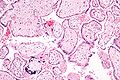

Micrograph of a placental infection (CMV placentitis).